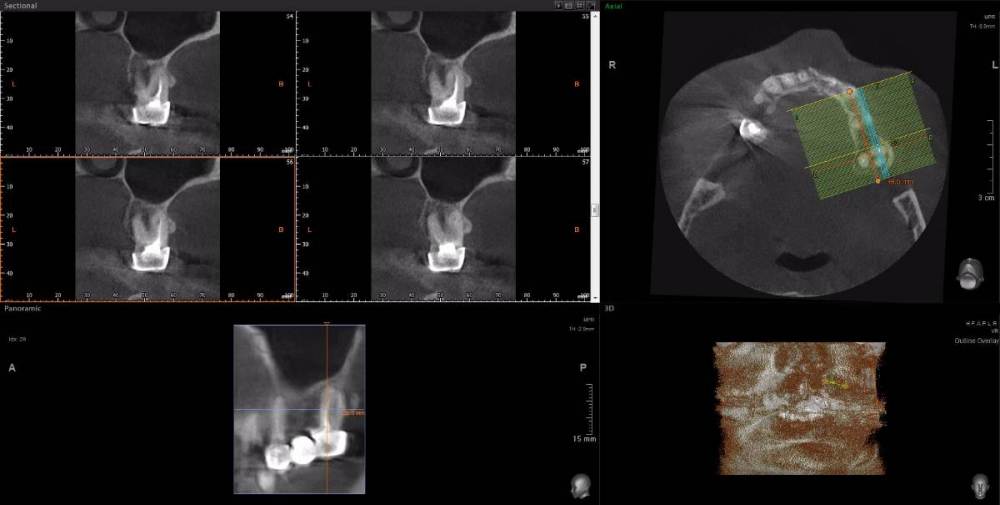

Dude Опубликовано 1 апреля, 2021 Поделиться Опубликовано 1 апреля, 2021 По плану в 1 этапе, кроме остального: лечение каналов и укрепление их стекловолоконными штифтами: 16, 25, 27, 44, 47; имплантация 14, 15, 17, 12, 11, 21, 22, 24, 26, 36, 37, 46, 45. Во 2 этапе (через 5-6 месяцев) установка коронок. Лечение в другой стране. Чтобы сократить длительность первого этапа, предложили лечение зубов сделать на 2 этапе. Очень засомневался, можно делать имплантацию с невылеченными зубами? Ссылка на комментарий

wladdX Опубликовано 1 апреля, 2021 Поделиться Опубликовано 1 апреля, 2021 Я бы повторное лечение к\каналов рекомендовал провести до хирургии. Конечно, может быть и другое мнение. Скрытый текст 1 Ссылка на комментарий